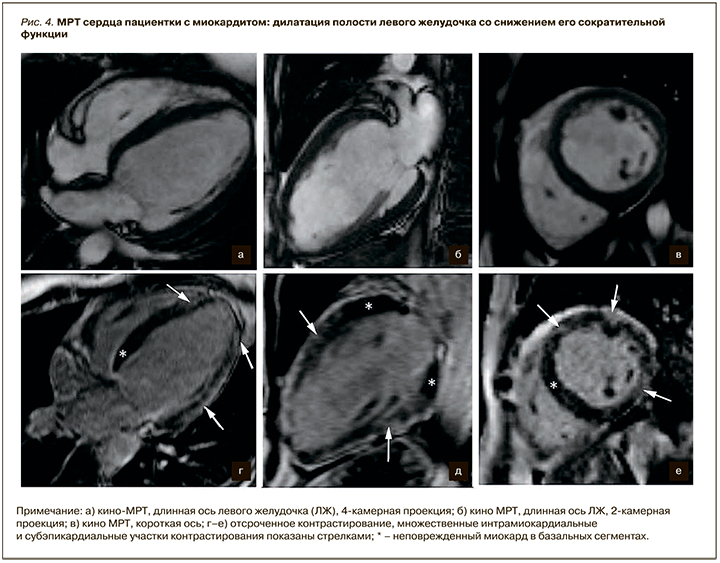

Субэндокардиальный характер контрастирования не типичен для миокардита, что позволяет проводить дифференциальный диагноз с постишемическими рубцовыми изменениями миокарда. Участки накопления контрастного препарата могут определяться субэпикардиально или интрамурально в нижнебоковом (наиболее часто) и переднеперегородочном (реже) сегментах; могут быть множественными или диффузными (рис. 4).